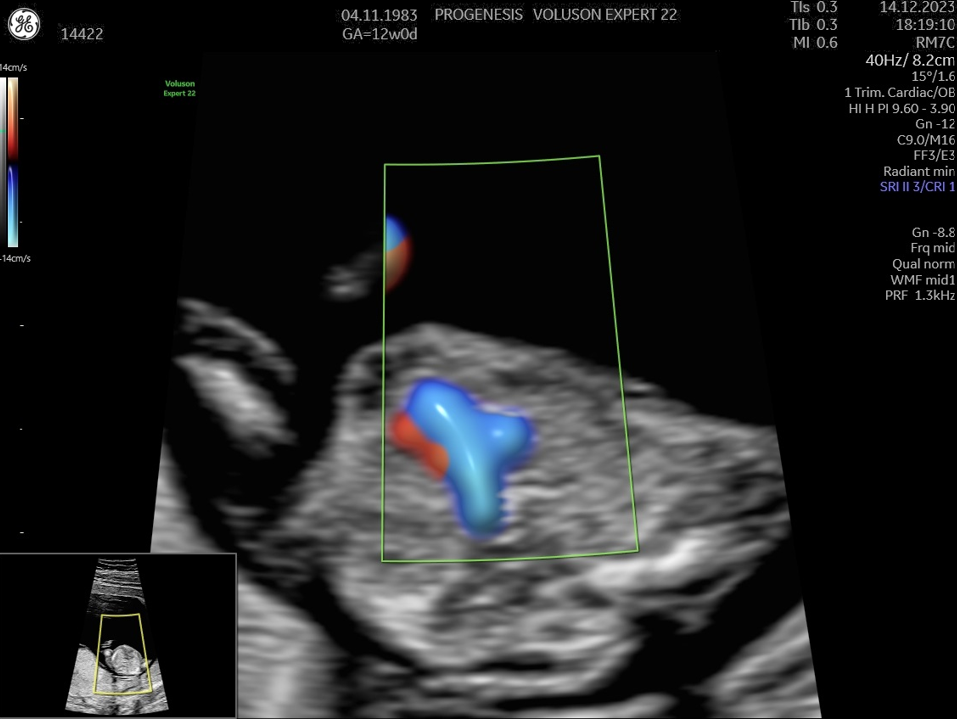

Πολλές και σημαντικές ανωμαλίες, όπως ανεγκεφαλία, απουσία άκρων, ομφαλοκήλη, ορισμένες συγγενείς καρδιοπάθειες και άλλες ανωμαλίες, είναι ορατές απ' αυτό το στάδιο της κύησης. Δίνουμε ιδιαίτερη έμφαση στην αξιολόγηση της καρδιάς των εμβρύων, τόσο για την αξιολόγηση χρωμοσωμικών ανωμαλιών όσο και πρώιμη ανίχνευση συγγενών καρδιοπαθειών από το 1ο κιόλας τρίμηνο (π.χ. υποπλασία καρδιάς, συγγενή μετάθεση μεγάλων αγγείων).